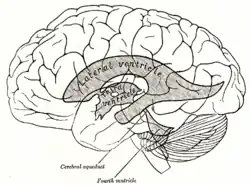

Срединный сагиттальный разрез головного мозга. Проекция желудочков головного мозга на его поверхность

Проекция желудочков головного мозга на его поверхность- Водопровод мозга